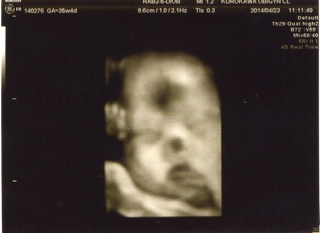

テーマ:赤ちゃん待ち 今日は黒川産婦人科の妊婦検診2回目! 9:15(午前中4番目)の予約でしたが、ちょっと早めに8:45頃受付。 診察券、母子手帳、3Dエコー用のDVDを受付に提出します。 採尿、血圧をした後、助産師さんに呼ばれ、体重測定。 約3週間で+1.6kg(トータル+7.7kg)と、絶賛増量中なわけでして…;^_^A やはり、注意されてしまいました〜(>_<) 診察室に呼ばれたのは10:00頃。 ※注意 ↓これより下にエコー画像があります。 ...

Pretty Happy | 2014.04.23 Wed 21:05